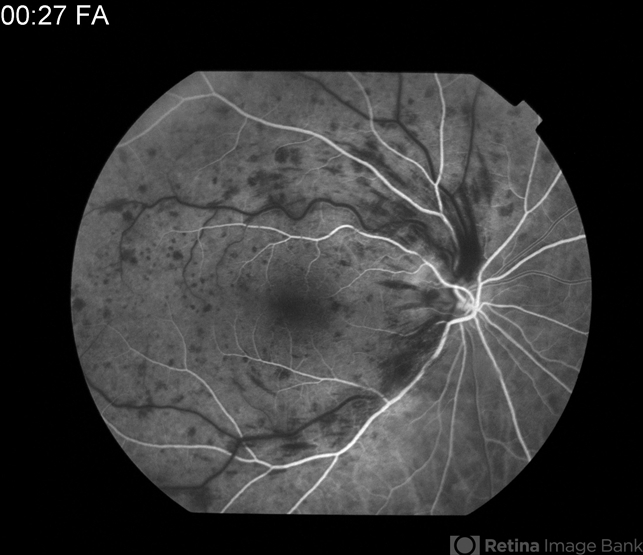

- CRVO

- central retinal vein occlusion (CRVO)

- Dye-Transit FA